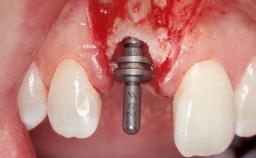

A 30-year-old female patient had lost tooth 21 and was referred to our clinic for consultation and treatment. Due to advanced apical infection, tooth 21 had been extracted two months earlier at another clinic and an acrylic-resin tooth had been bonded to the adjacent teeth. The patient desired implant treatment to avoid any damage to the adjacent natural teeth. While the patient had no history of any systemic disorder, she was a heavy smoker and exhibited medium to advanced periodontitis in the entire jaw. After the initial treatment to achieve a pocket probing depth of less than 4 mm and no bleeding on probing, a decrease in the height of the papillae mesial and distal to the extraction site and overall gingival recession were observed.

Type of Implants One-Piece|Reduced-Diameter

Bone Augmentation Horizontal|Staged

Augmentation Materials Autogenous chips|Membrane